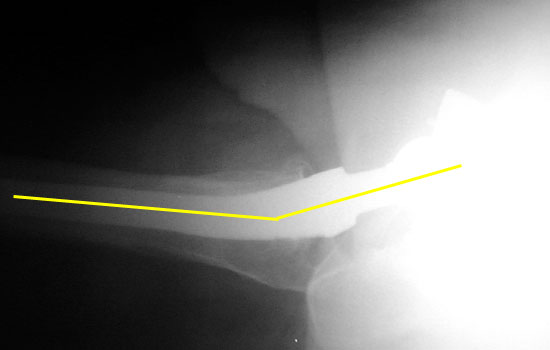

• Anteversion is difficult to accurately evaluate on radiographs, and can only be qualitatively assessed on a groin lateral view. This view is difficult to obtain, especially in the elderly or post operative patient, and is effected by pelvic or thigh rotation.

The right cup is normally anteverted, the left cup anterior and posterior rims are far apart, suggesting excessive anteversion.

R

L

Groin lateral films: R cup normal anteversion, L cup excessive anteversion